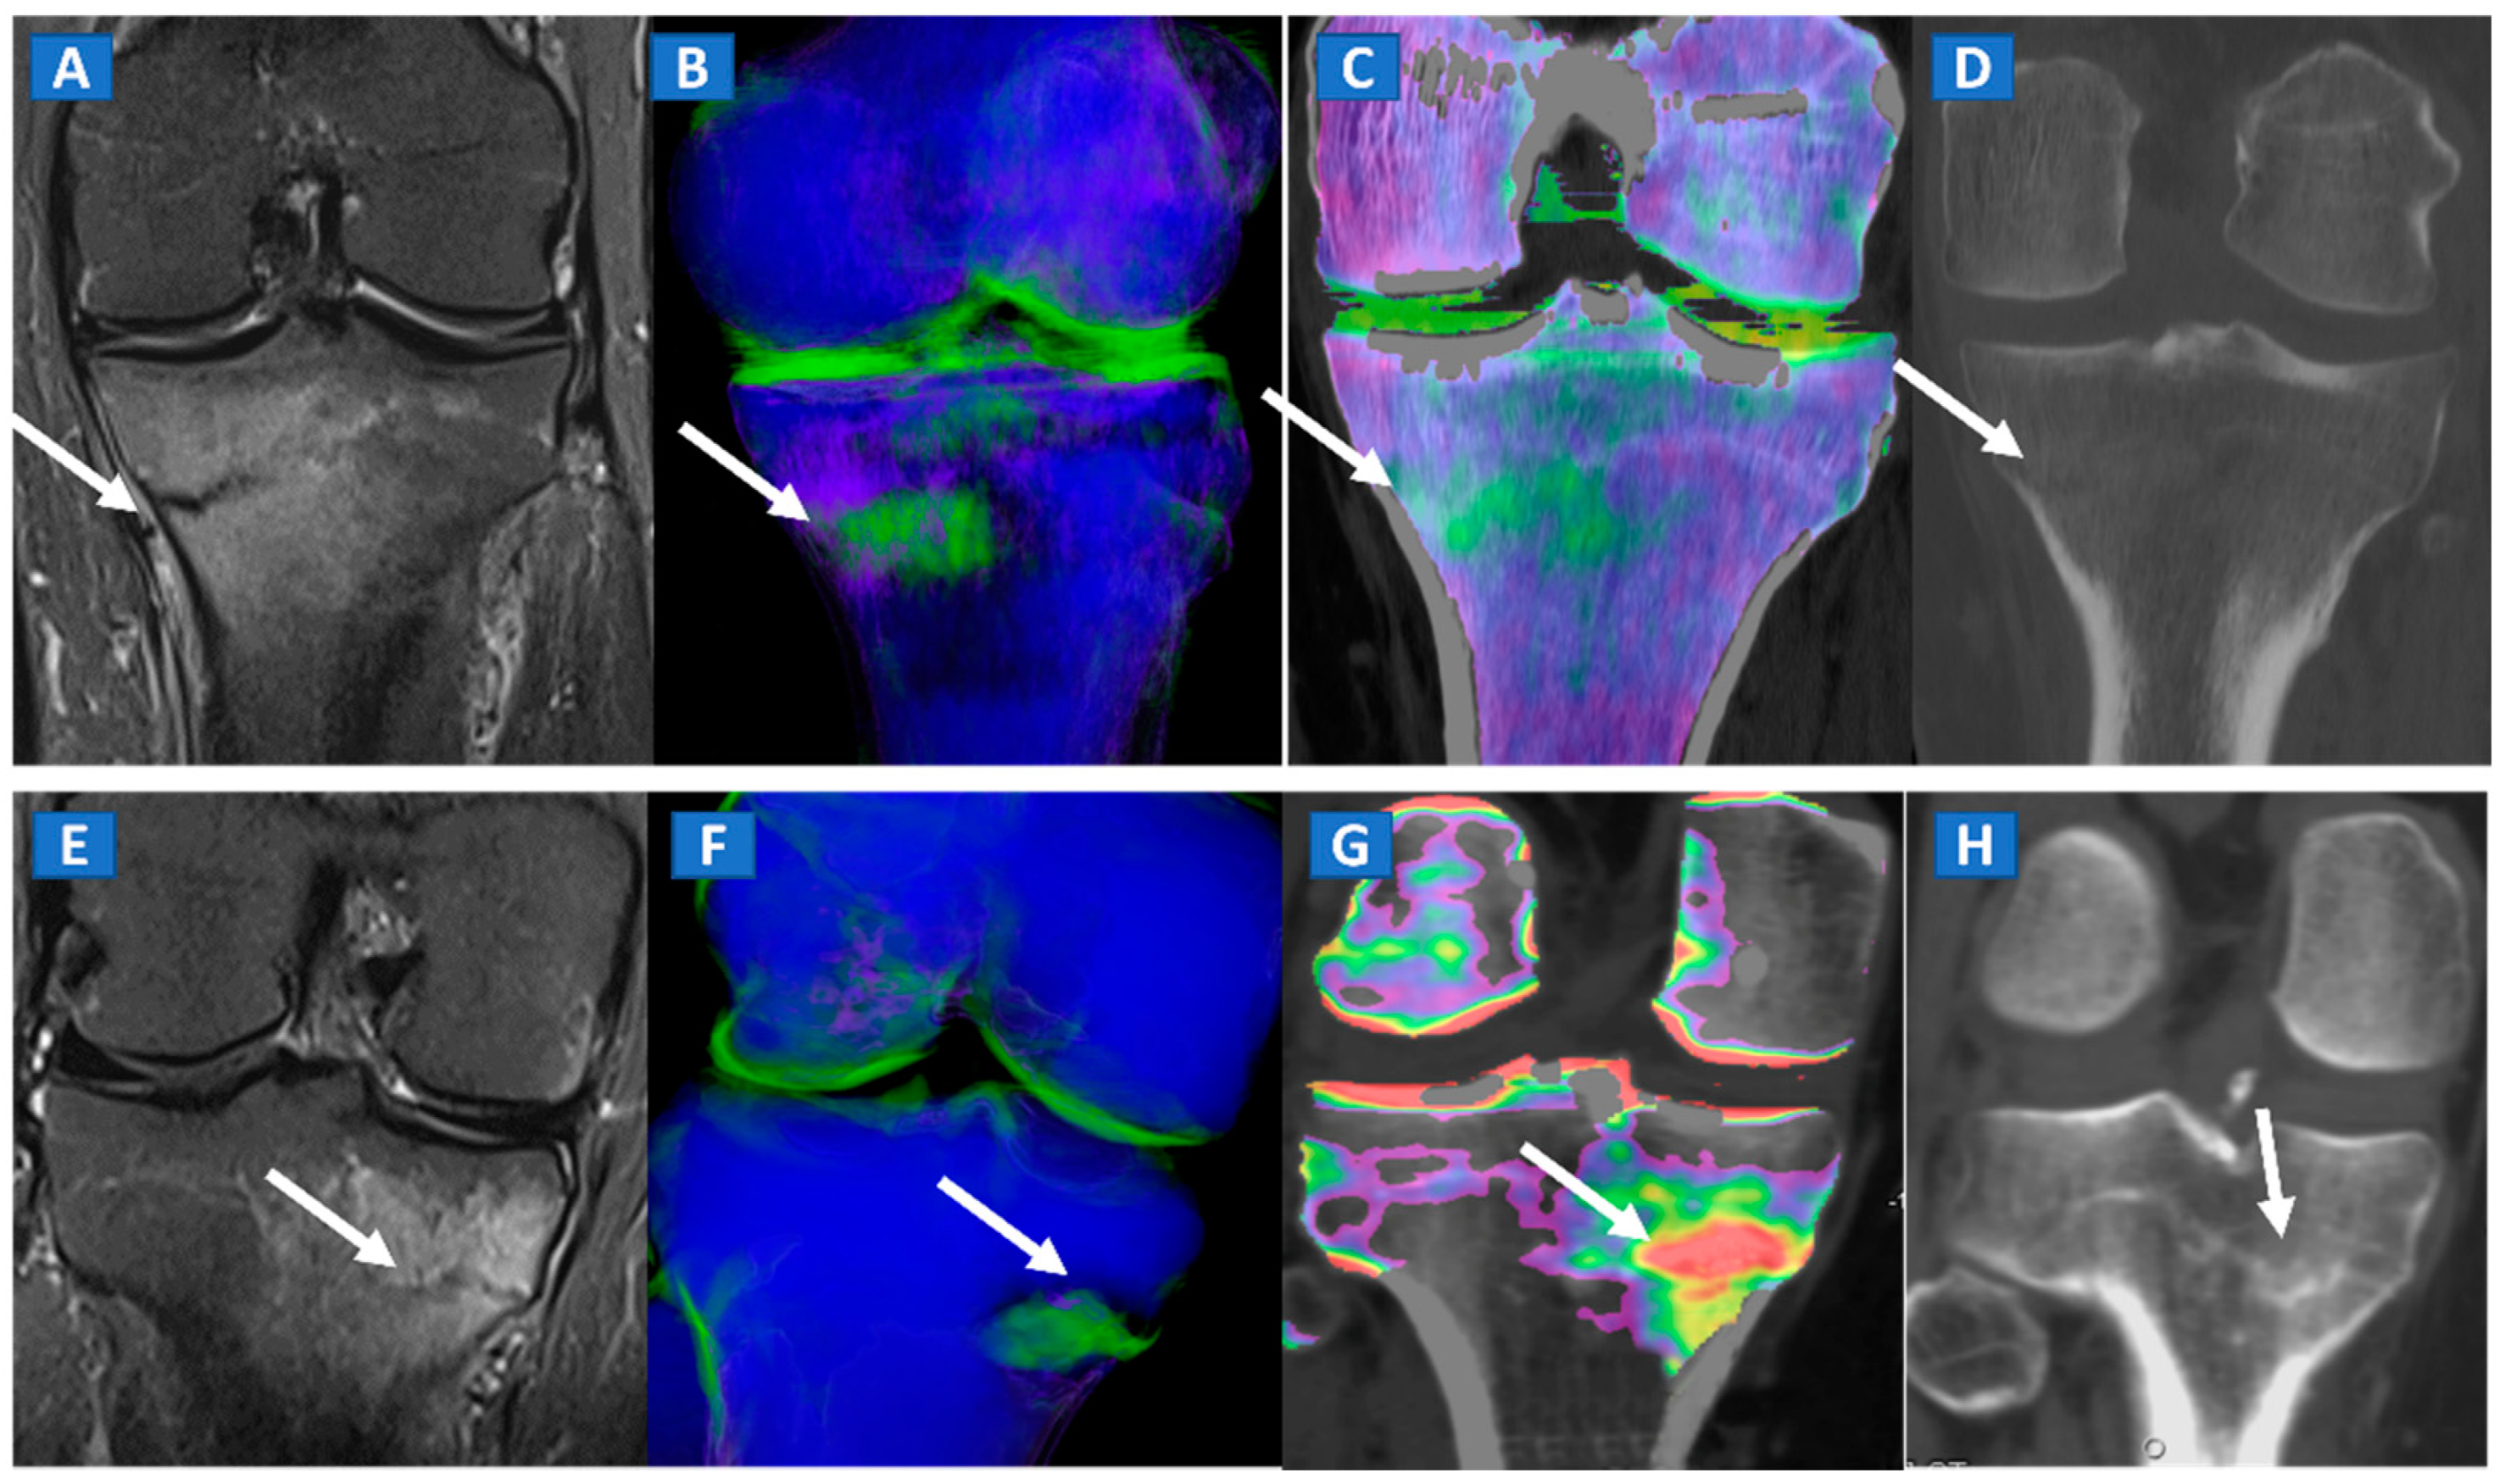

DECT has been successfully used to diagnose OCL of the knee and ankle both in traumatic and non-traumatic settings [3,7]. Painful OCL are typically associated with BME (Figure 3), often appearing as markedly edematous subchondral areas in DECT images, surrounded by milder and peripherally degrading BME [3,7]. However, some OCL can be missed by DECT, especially in the presence of subchondral sclerosis [8]. The analysis of additional associated findings, such as articular space narrowing that is typical of patients with osteoarthritis or meniscal or ligamentous injuries, may help in the identification of smaller, less obvious BME foci (Figure 4). In such cases, color-coding spared bone in violet and BME in shades of green, and correctly adjusting the level of superimposed BME information are key to an accurate diagnosis.

Figure 3.

Figure 4.

A 65-year-old female with non-traumatic medial-sided knee pain. On the coronal STIR MRI image (A) the body of the medial meniscus is ruptured and medially dislocated (thick arrow). Tiny, subtle BME areas can be seen on the femoral condyle (thin arrow) due to advanced chondropathy. Tiny areas of BME (thin arrow) are also depicted on the corresponding coronal 1 mm reconstructed DECT image (B). By using alternative color-coding (C), DECT allows the depiction of the ruptured meniscus (thick arrow), providing a good correlation with MRI findings.

A 42-year-old male long-distance runner with a bilateral tibial stress fracture. On the coronal STIR MRI images (A,E), a hypointense serpiginous subchondral line (arrows), surrounded by subtle BME involving the proximal tibia on the medial side, is depicted. On the DECT 3D maps (B,F) some BME is apparent around the fractures (arrows). On the corresponding DECT coronal 2D images (C,G), the presence of BME is confirmed (arrows), with a periphery to center gradient. The standard coronal reconstructed CT images (D,H) confirm the fracture lines (arrows). Note the absence of reactive sclerosis in the left knee (D) and the presence of sclerosis in the right one (H).